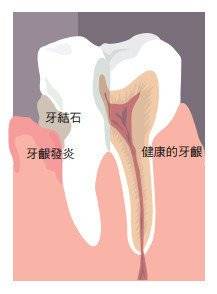

其次,决定正畸能否进行的关键是牙周状况。

一般来说,牙周是牙齿周围的骨组织、牙龈组织和连接牙齿与它们的韧带组织。

他们的健康状况将直接影响正畸风险的评估和治疗策略的制定。

日常口腔卫生维护,定期洗牙或刮牙是保持良好牙周健康的利器。

牙齿正畸过程中的所有牙齿移动和牙齿维护阶段的再稳定

都需要良好的牙槽骨重建,

而牙龈组织直接影响牙齿的美观。

这就是为什么牙周状况是正畸治疗的重要参考因素之一。